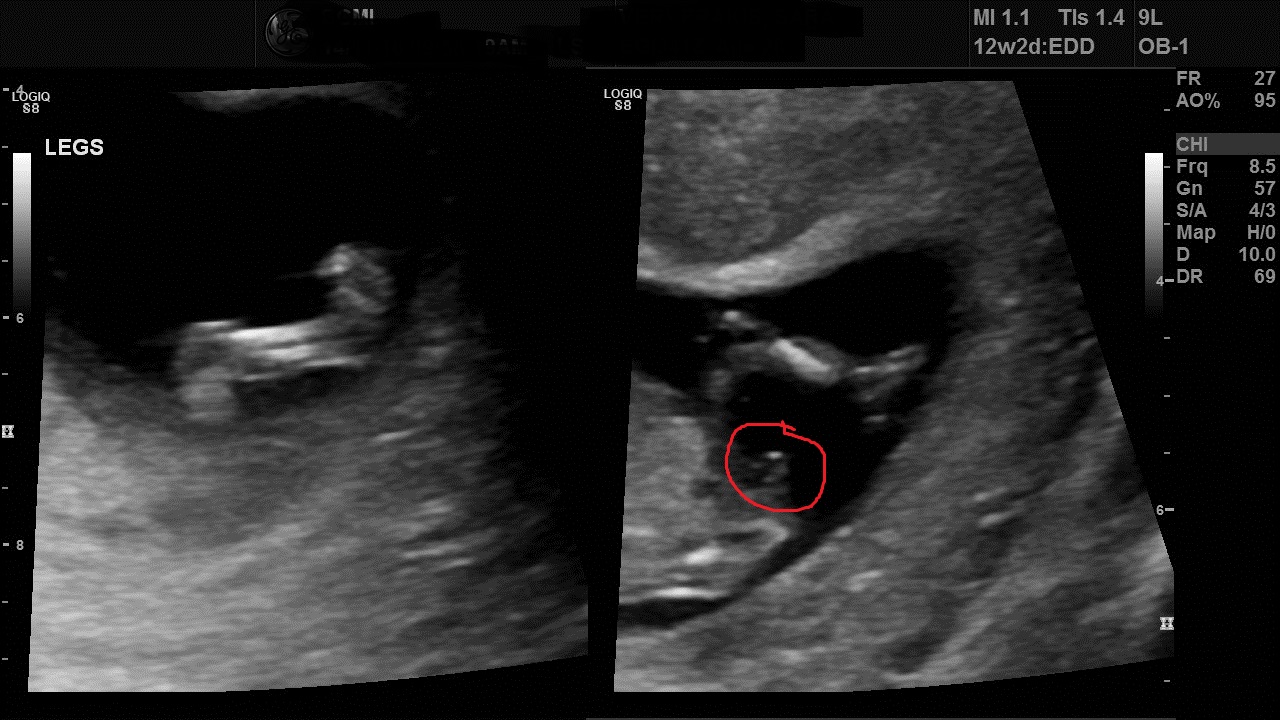

I had my 12 week scan and the tech said she thinks i am having a boy. Though she also said it may be the umbilical cord as my first son didn't look like this, it looked more like a turtle. I have posted profile and potty shot. it looks like a nub to me in the potty shot. Thanks

Also attached leg photos. I have circled what i think looks like a nub. Do you think it looks like a boy nub?Attachment 33748